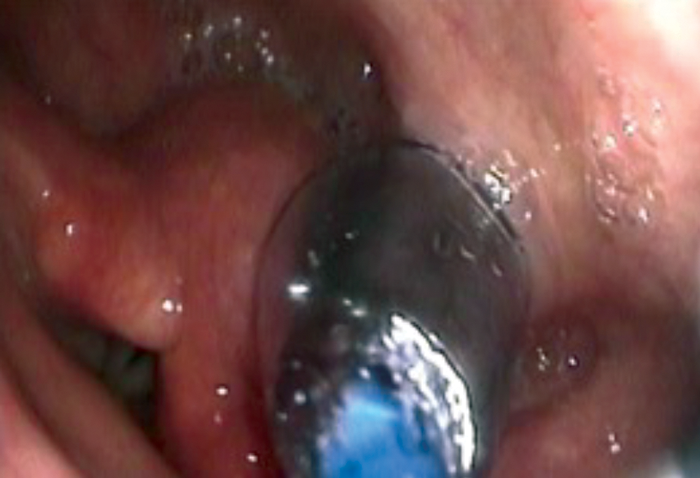

Once the tip of the guide wire is placed beyond the stricture, the TNO is reintroduced nasally via the most patent nasal cavity to visualise the pharynx during the dilatation. The uninflated balloon is then passed over the guide wire nasally until it passes through the area to be dilated. Both TNO and the balloon cables may be passed via same nostril if the other nostril is too narrow. The balloon is positioned with the proximal metallic silver marker visible just above the level to be dilated (see Figure 5). The balloon is then inflated using the pressure pump syringe until 20mm full dilatation (see Figure 6). This is then deflated after one minute and the balloon is removed with the guide wire. In some cases of webbing or cricopharyngeal bar, two 20mm balloons (40mm maximum) may be used simultaneously (see Figure 7). However, this carries a higher risk of perforation and it is more painful and, therefore, will need sedation in addition to the local anaesthesia.

Figure 5. Balloon being positioned in the cricopharynx.

Figure 6. Single balloon dilatation of a cricopharyngeal web.